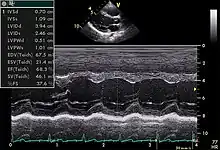

Motion mode is infrequently used in modern echocardiography. It has specific uses and has the benefit of very high temporal fidelity (eg, measuring LV size at end diastole).